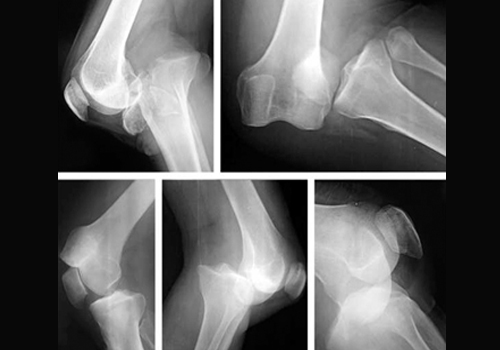

بیماری های مفصلی

Joint diseases